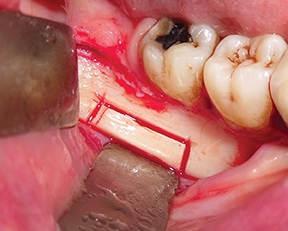

A full-thickness trapezoidal flap was elevated to expose the recipient site (Fig. 4). After releasing all muscular attachments, flap extension was checked coronally (Fig. 5).

Fig. 4: Intraoral view of the atrophic bone area

Fig. 5: Extent of flap release